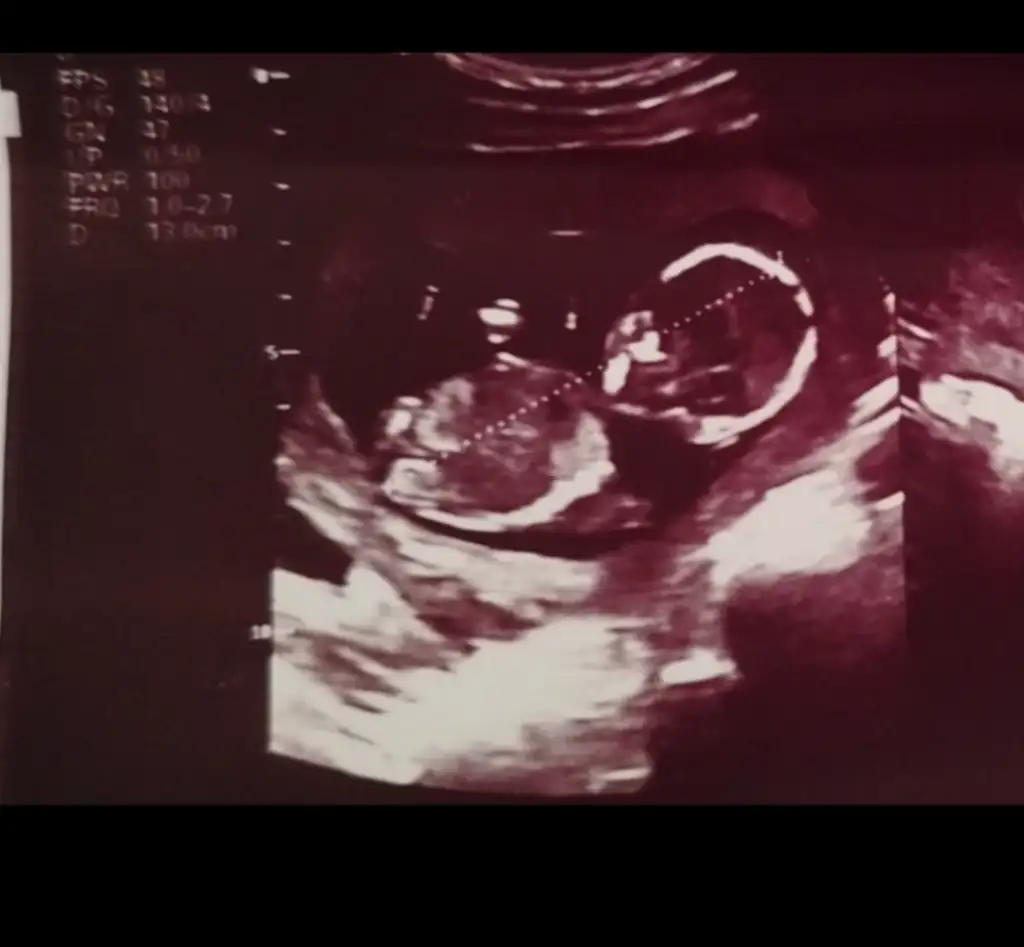

Öncelikle sağlıklı olsun, bana kiz gibi geldiHerkese merhaba lütfen cinsiyyet tespiti yaparmısınız yaparsanız çok sevinirim çok merak ediyorum14 haftalığız şu an ama doktor cinsiyyetini söylemedi(

Kız bence nub aşağı bakıyorHerkese merhaba lütfen cinsiyyet tespiti yaparmısınız yaparsanız çok sevinirim çok merak ediyorum14 haftalığız şu an ama doktor cinsiyyetini söylemedi(

Nasıl anladınız yan görüntüsünde nubu dik görünmesi gerekmez miydi bacakları yukarıda diye görünmemiş olabilir mi? Teşekkür ederim yorumunuz içinErkek bence

Bana dik geldi kaç haftalık?Nasıl anladınız yan görüntüsünde nubu dik görünmesi gerekmez miydi bacakları yukarıda diye görünmemiş olabilir mi? Teşekkür ederim yorumunuz için

13+2 ultrasondaBana dik geldi kaç haftalık?